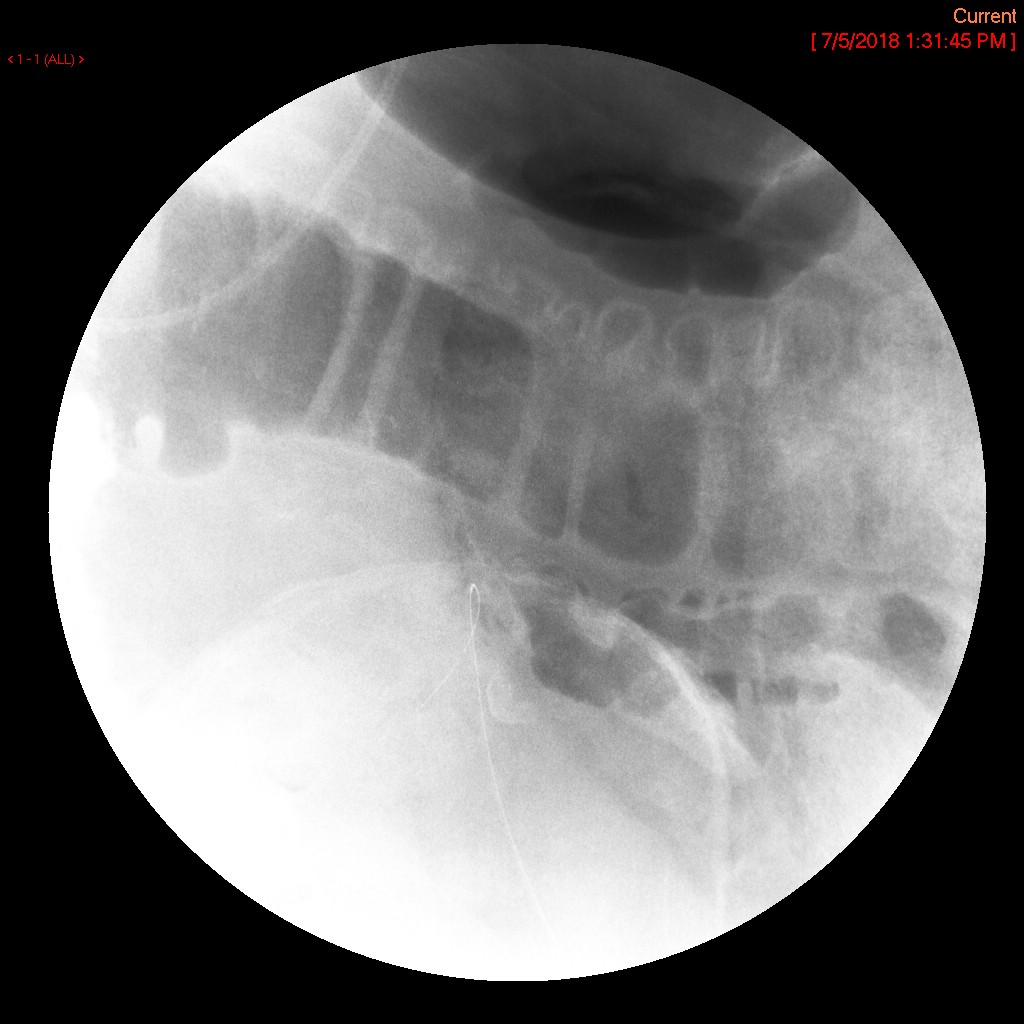

- The technologist will obtain a scout radiograph to include the upper abdomen. Evaluate for the location of the surgical chain sutures

(key image 1).

- There are usually two "sets" of surgical chain sutures.

- The first is located in the epigastric area at the level of the gastrojejunal anastomosis.

- The second is usually located in the left midabdomen. This is the site of the jejunojejunal anastomosis.

- The technologist will take a post procedure radiograph to evaluate the upper abdomen

(key image 4).

- If the contrast material has not progressed beyond the jejunojejunal anastomosis on the first radiograph, have the technologist obtain a delayed radiograph (more than one may be needed). Once the contrast has progressed past the jejunojejunal anastomosis, the procedure is complete

(key image 5)

(key image 6)

(key image 7).